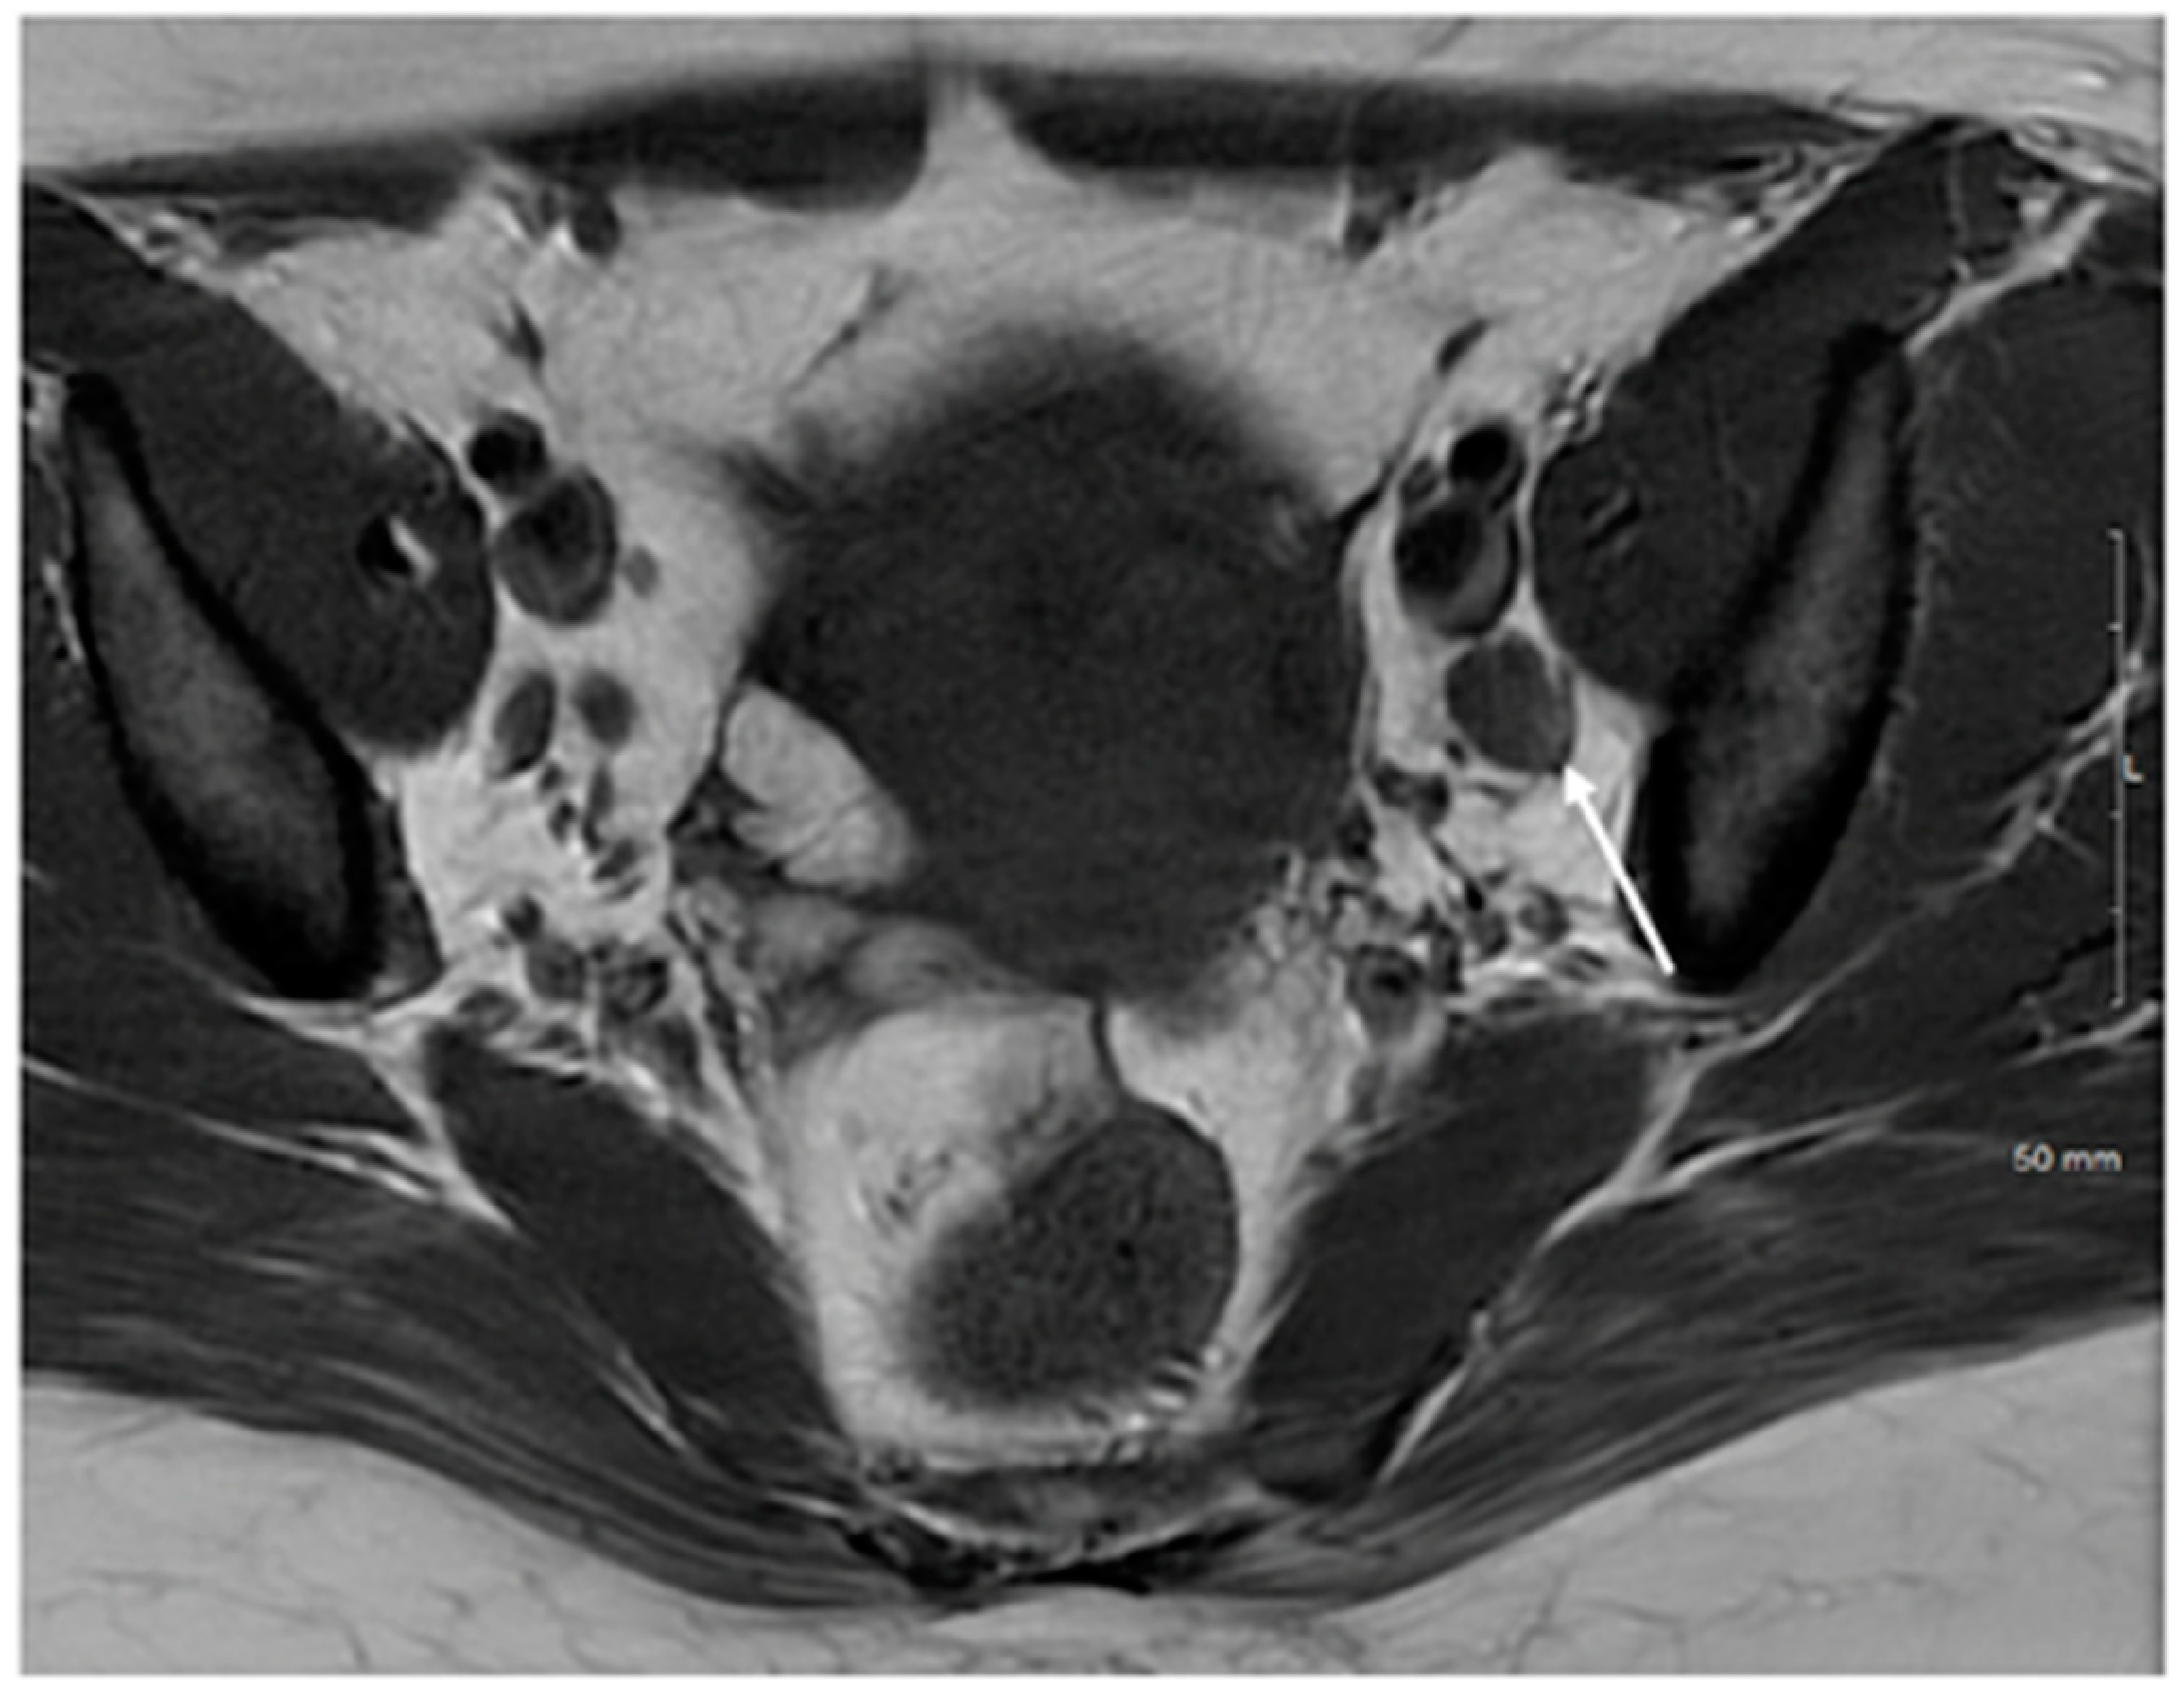

| Stage IV | Spread to adjacent and distant organs |

| IVA | Rectal or bladder involvement |